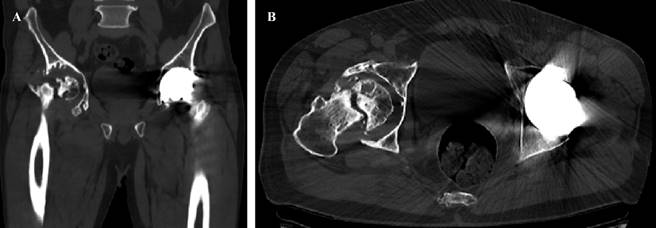

Se realiza radiografía anteroposterior (AP) de pelvis donde se observa pérdida de la esfericidad de la cabeza femoral, presencia de osteofitos, esclerosis con colapso subcondral, disminución del espacio articular, todo compatible con cambios degenerativos avanzados que se acompañan de cambios acetabulares secundarios a la osteonecrosis. En la cadera izquierda se observan componentes protésicos acetabular y femoral adecuadamente colocados y orientados, sin datos de interfaz, lisis o aflojamiento (Figura 1). Para identificar adecuadamente la morfología femoral y acetabular, se toma tomografía computarizada donde se aprecian múltiples quistes subcondrales, así como defecto óseo contenido, con pérdida considerable de hueso esponjoso principalmente de la pared posterior (Figura 2).

Figura 2: Tomografía computarizada simple de pelvis para precisar características del defecto acetabular derecho. A) corte coronal en el que se observa defecto acetabular con presencia de múltiples quistes subcondrales. B) corte axial en el que se evidencia defecto acetabular predominantemente de la pared posterior y compromiso parcial de la columna posterior.